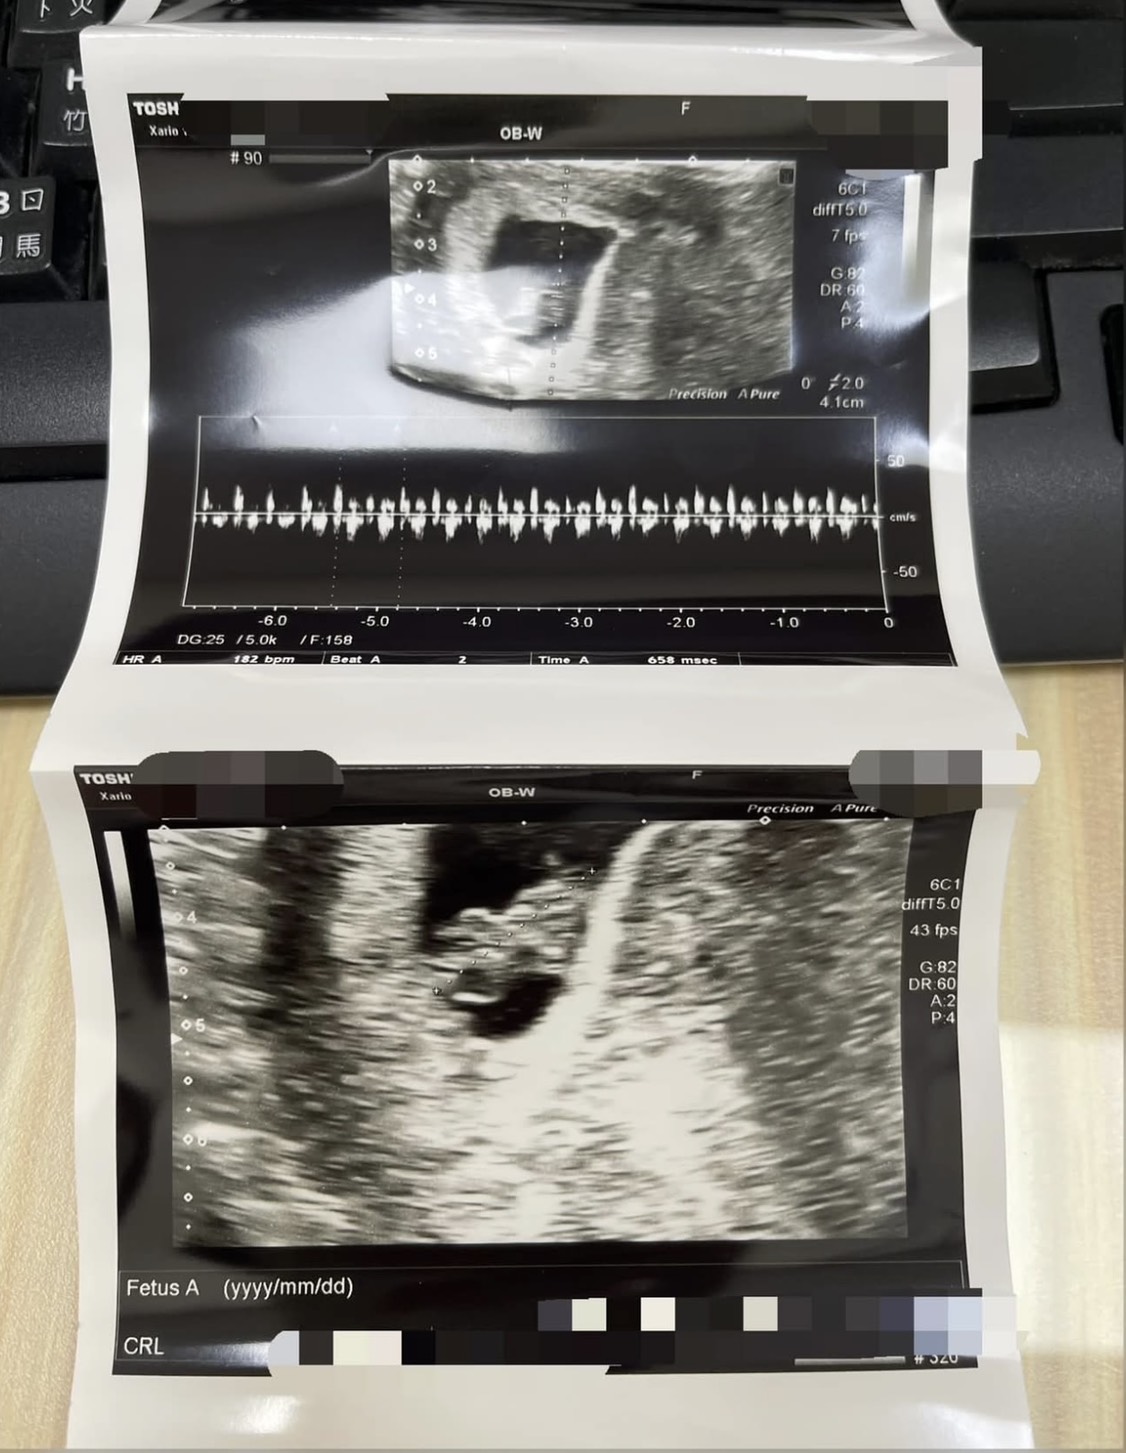

▶️C小姐在月經前情緒起伏大,容易焦慮,排便不順暢,腸胃脹氣,經過詳細診察辨證後為肝脾氣滯鬱化熱型,給予適合之中藥治療後,月經前無異常滴滴答答出血,基礎體溫穩定長達14天(黃體功能恢復正常),配合排卵期計畫性受孕成功。懷孕後持續服用中藥安胎,目前胎兒已經超過三個月大,穩定成長中。

圖片為患者懷孕時分享給蘇醫師的超音波檢查照片。